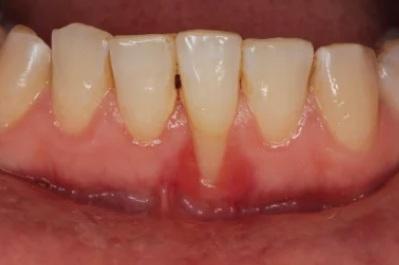

Resesi gingiva adalah kondisi ketika gusi mengalami penyusutan atau penurunan sehingga akar gigi terlihat lebih jelas.

Selain menimbulkan perubahan pada senyum, resesi gusi bisa membuat gigi menjadi lebih sensitif, perdarahan saat sikat gigi, hingga bau mulut yang sulit hilang.

Selain akar gigi yang terlihat, berikut adalah gejala lain dari resesi gingiva.

- Gusi berdarah setelah sikat gigi atau flossing.

- Nyeri pada garis gusi.

- Gusi bengkak dan merah.

- Bau mulut.

- Peningkatan sensitivitas pada makanan dan minuman panas, dingin, atau manis.

- Gigi goyang.